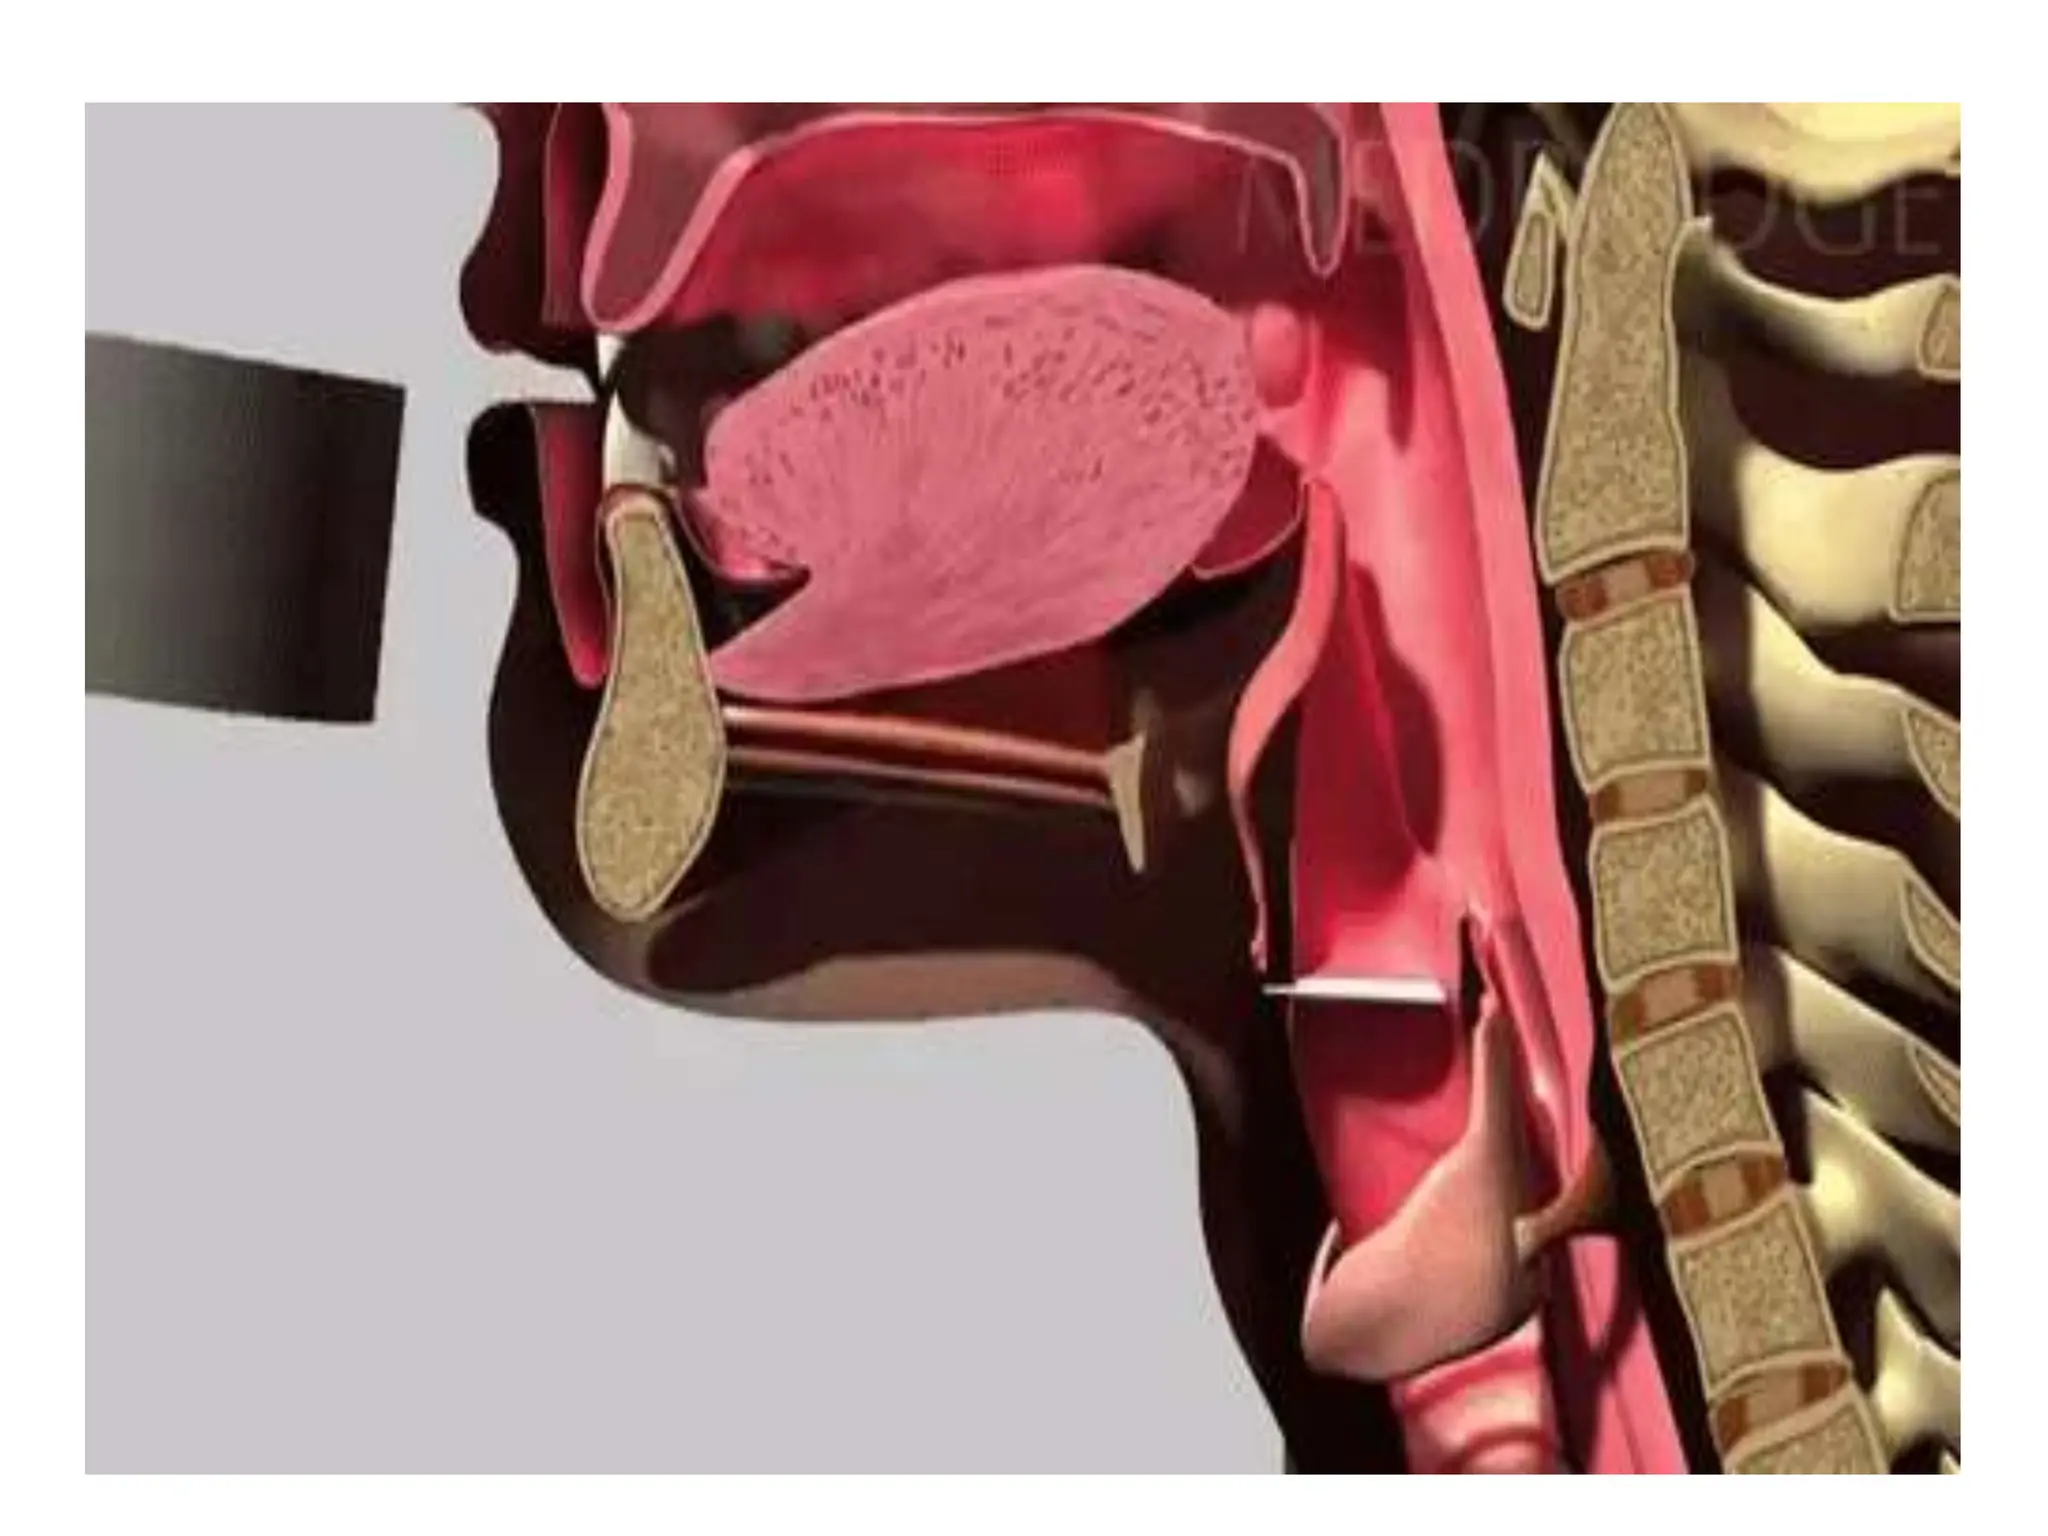

Pharyngeal phase

• Involuntary

• Soft palate moves upward

• Epiglottis moves backward

• Vocal cord approximates

Upper esophageal sphincter muscles relaxes

• Bolus of food is

moved to

esophagus via

constriction of

pharyngeal

constrictor muscles